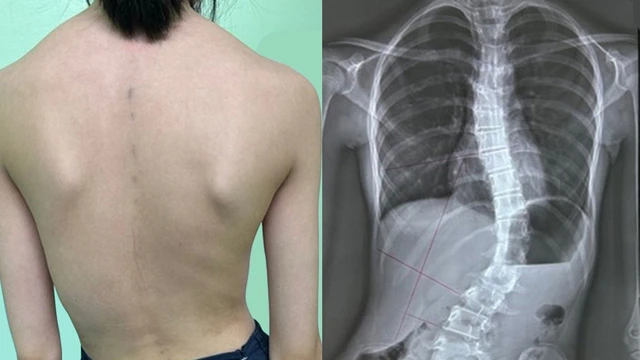

Tình trạng vẹo cột sống bất thường ngày càng phổ biến, đặc biệt ở trẻ em. Không chỉ gây bất tiện trong sinh hoạt, vẹo cột sống còn ảnh hưởng nghiêm trọng đến chức năng của các cơ quan xung quanh. Vì thế, nắm rõ dấu hiệu vẹo cột sống là chìa khóa giúp phát hiện sớm, can thiệp kịp thời để giảm tối đa nguy cơ biến chứng.

Bệnh vẹo cột sống là tình trạng cột sống mất đi đường cong sinh lý bình thường. Chẩn đoán dựa bởi tình trạng cong vẹo cột sống trên lâm sàng và X-quang cột sống thắt lưng. Điều trị chứng vẹo cột sống phụ thuộc vào mức độ nặng của độ cong vẹo cột sống. Đây là một bệnh lý tương đối phổ biến ở giới trẻ hiện nay.